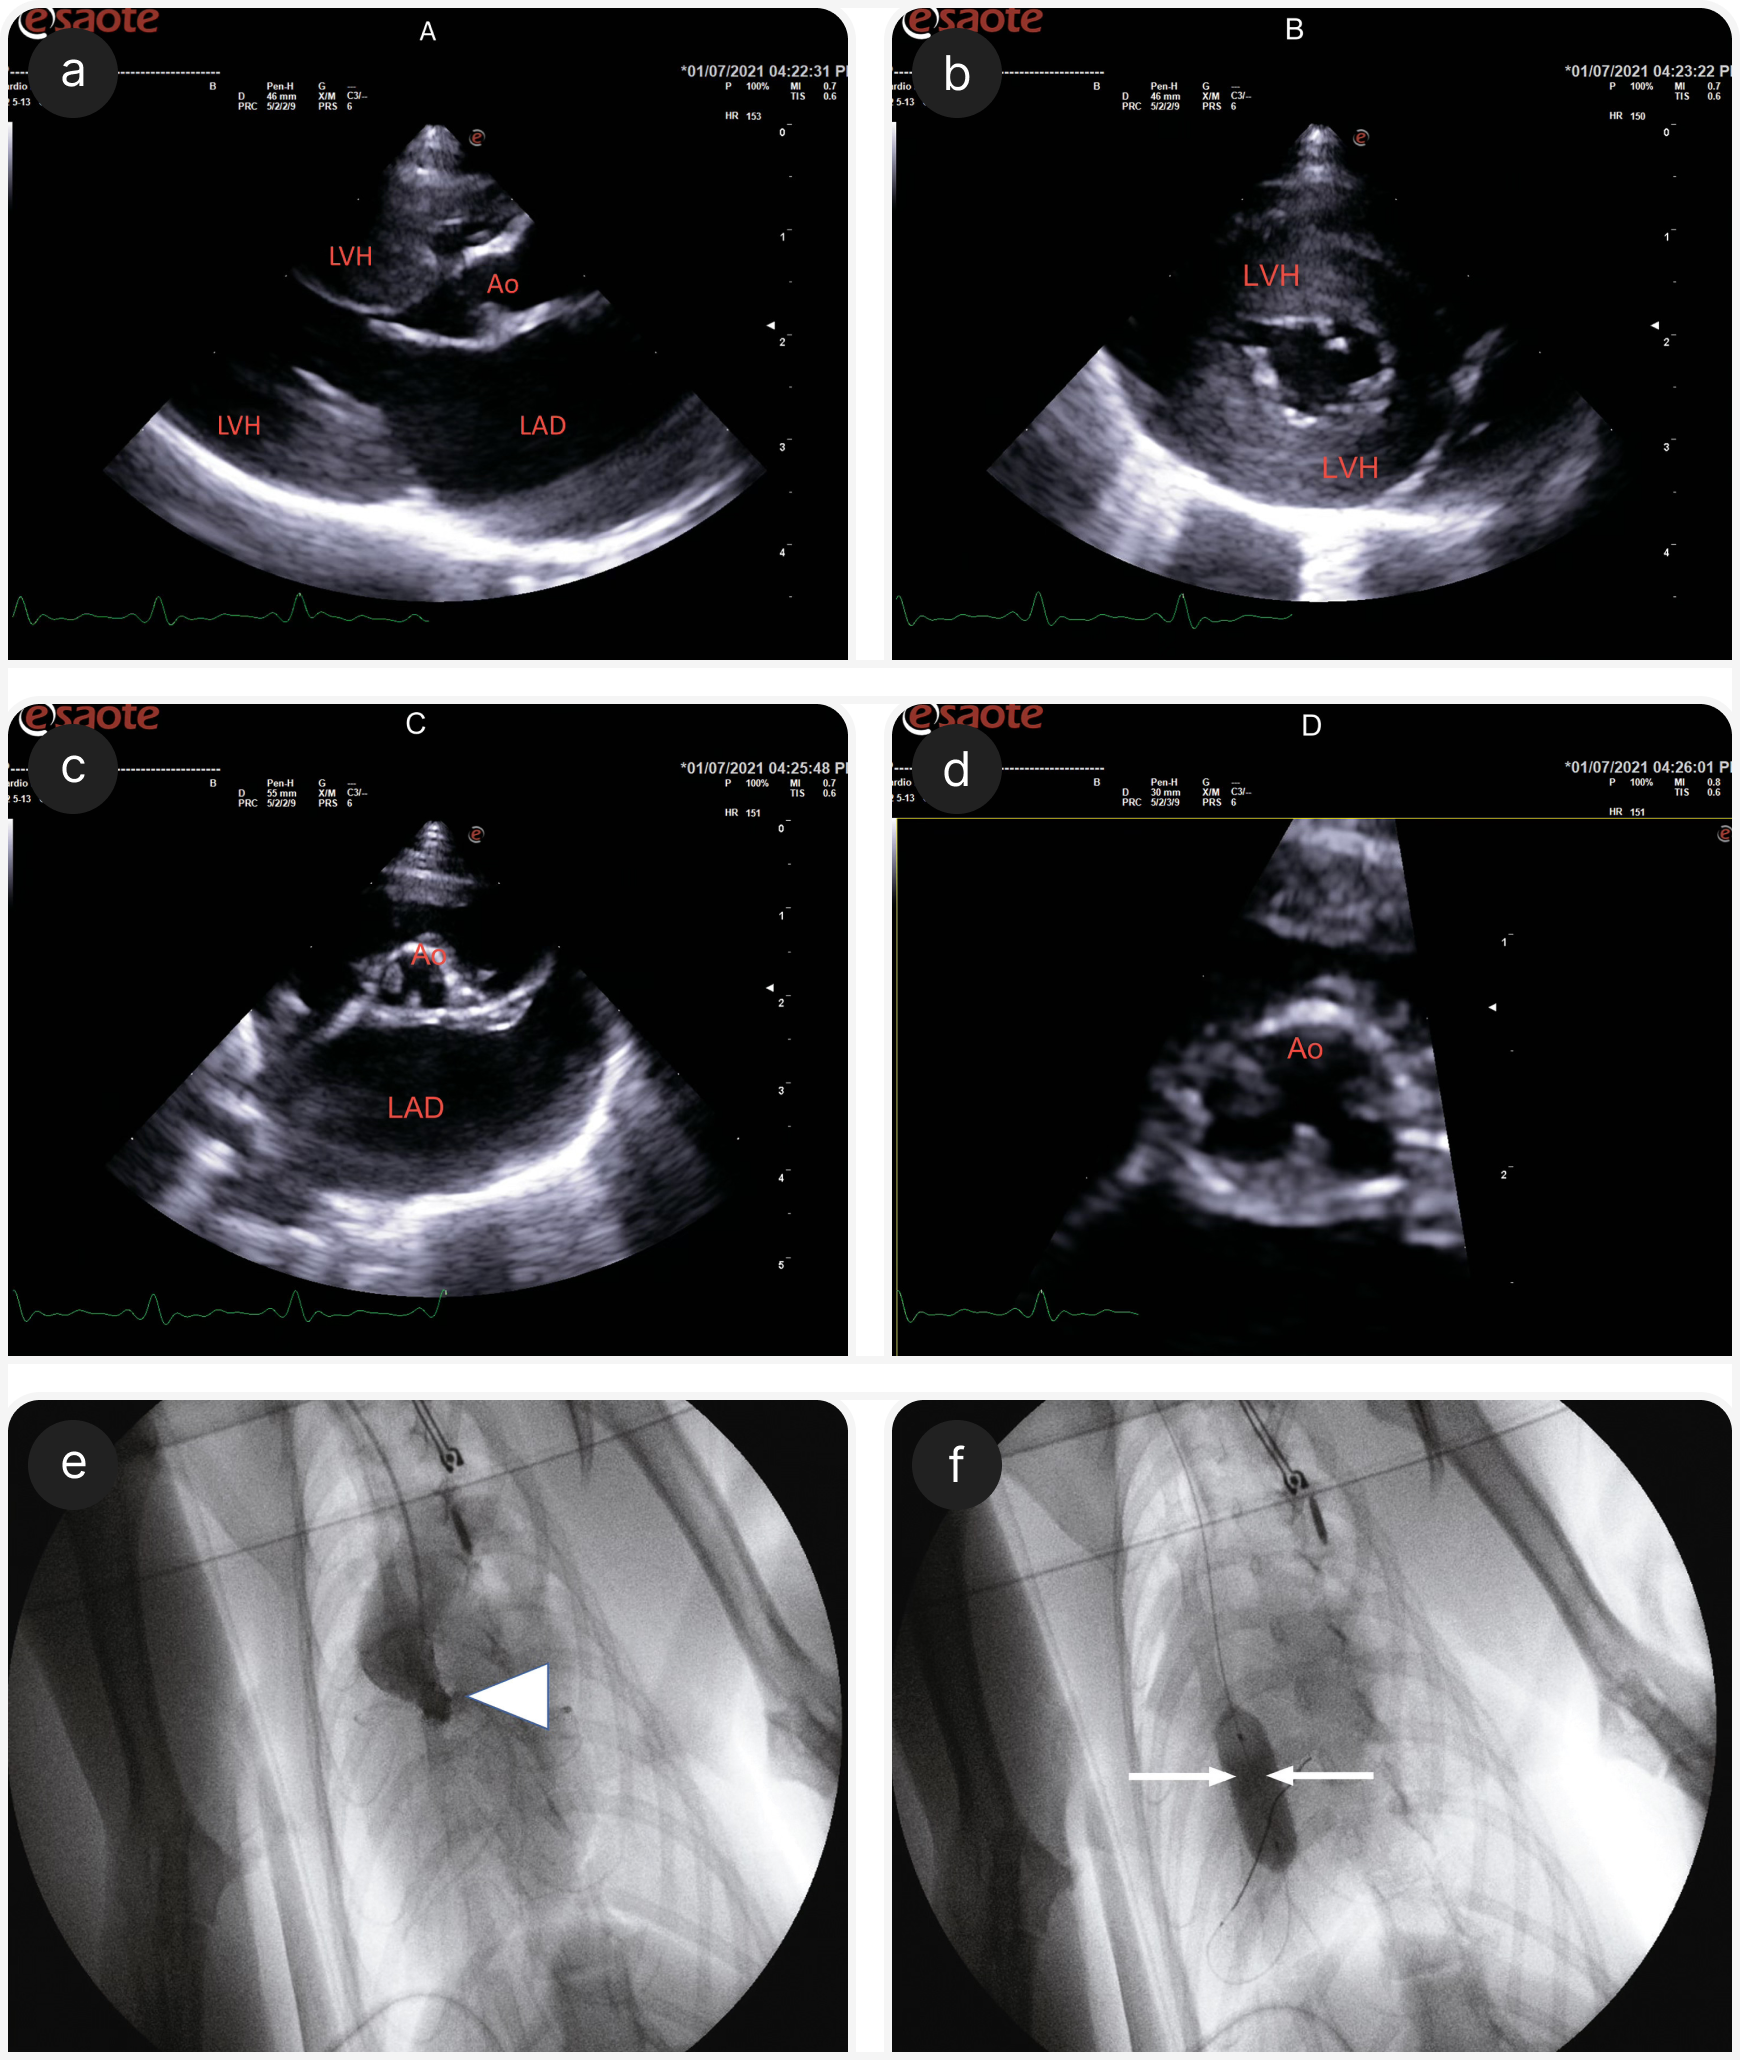

Динамическая обструкция выходного тракта правого желудочка (DRVOTO) — еще один частый симптом у кошачьих, причем у них это состояние оказывается полностью доброкачественным (17, 18) и не сопровождается обмороками. Обморок вследствие обструкции выходного тракта сердца у кошек также описан в случаях дирофиляриоза (9) и тяжелого аортального стеноза (Рисунок 4).

В большинстве случаев обморока у кошек на фоне брадикардии методом выбора станет имплантация постоянного кардиостимулятора. Собакам электрокардиостимулятор чаще всего имплантируют трансвенозно, устанавливая электрод кардиостимулятора в верхушке правого желудочка, но у кошек выше предрасположенность к осложнениям, таким как синдром краниальной полой вены с хилотораксом, обструкция выходного тракта правого желудочка и внутрисердечный тромбоз (4, 26). Поэтому у кошек наиболее распространенным методом имплантации кардиостимулятора в настоящее время считают хирургическое размещение эпикардиального электрода путем торакотомии, которое редко сопровождается осложнениями.

Фиксированные обструкции выходного тракта, такие как аортальный и легочный стеноз, можно уменьшить с помощью баллонной вальвулопластики — минимально инвазивного вмешательства с использованием катетера с баллоном на конце, раздуваемого на уровне стенозированного клапана для растяжения и открытия частично сросшихся створок. У кошек динамическая обструкция выходного тракта очень редко сопровождается обмороком, но если удается задокументировать причинно-следственную связь, для уменьшения выраженности обструкции можно попытаться использовать бета-блокаторы (например, атенолол).

Автор выражает благодарность доктору Хайди Ферасин за помощь в ведении некоторых из описываемых клинических наблюдений и за неоценимую помощь в написании этой рукописи. Автор выражает особую благодарность доктору Даниэлле Маккриди, которая провела хирургическую имплантацию кардиостимулятора, показанную на Рисунке 3.